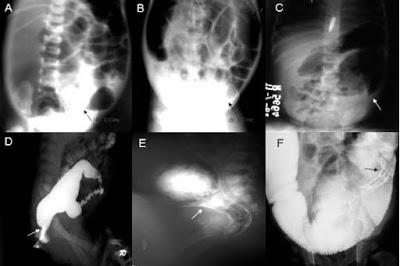

Radiografías abdominales de las distintas zonas del colon y enemas en la fila inferior

Según lo contado, últimamente tenía dolor abdominal, meteorismo (es decir, la acumulación excesiva de gases) y dificultad para respirar. La autopsia descubrió que el colon medía 254 centímetros y su circunferencia, en distintas zonas: 38 centímetros en el colon ascendente, aumentando gradualmente en el colon transverso hasta los 76'2 centímetros, disminuyendo en el colon descentente a 63,5 para aumentar de nuevo en el colon sigmoide a 68,58, con un recto de tamaño normal.

El mesocolon, la capa revestida de peritoneo que fija la pared posterior del abdomen, también era anormalmente grande y ancho. El colon contenía dos cubos y medios de heces que pesaban 18,1437 kilogramos. Las otras vísceras, aunque normales, se habían desplazado para acomodar al colon. A pesar de todo, el dr. Formad no observó pruebas de una obstrucción, como en una dilatación típica por la retención de heces, sino en un crecimiento excesivo del colon.